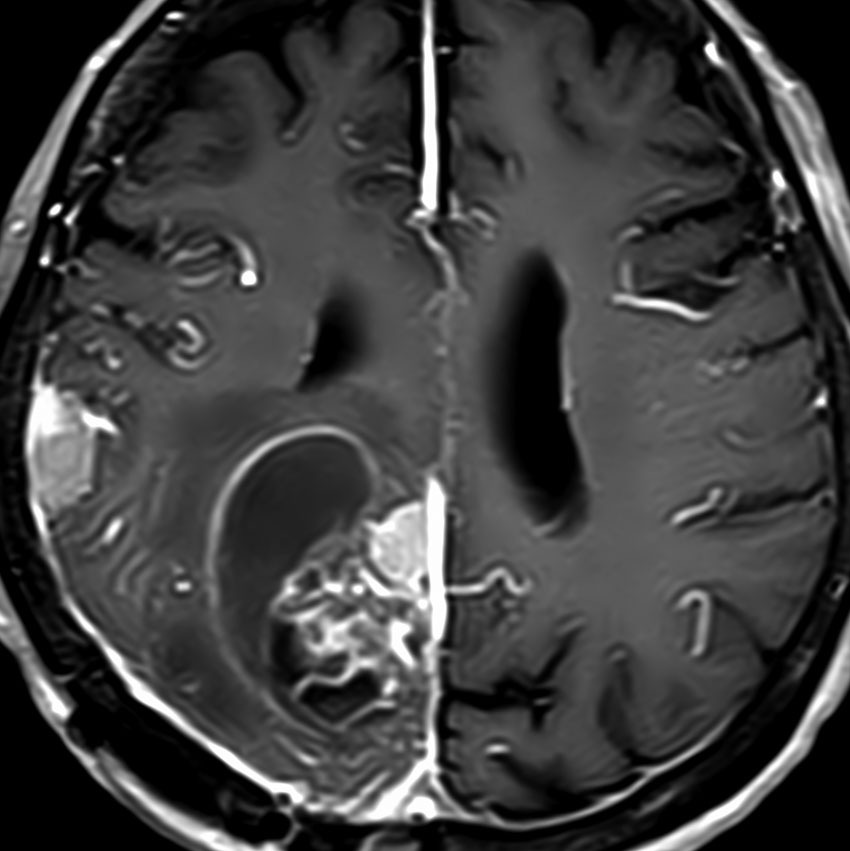

静脈洞交会 confluence に浸潤しているものです。直静脈洞は閉塞しています。右のMRIでは,ガドリニウム増強像が強弱まばらになっています。髄膜腫と診断したいのですが,ちょっと何かが違うというのがSFTです。硬膜や骨や脳に浸潤性格を有します。亜全摘出して術後に54グレイの放射線治療をしました。

5年後に小脳内に再発しました。全摘出したのですが,その後もあちこちに再発を繰り返しています。最初はグレード2でしたが,再発を繰り返すと増大速度が速くなり,再発までの期間が短くなり,多発性再発となってきます。